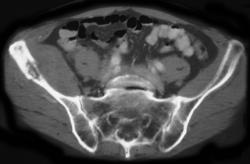

Fracture of Transverse Process of L3 With Hematoma